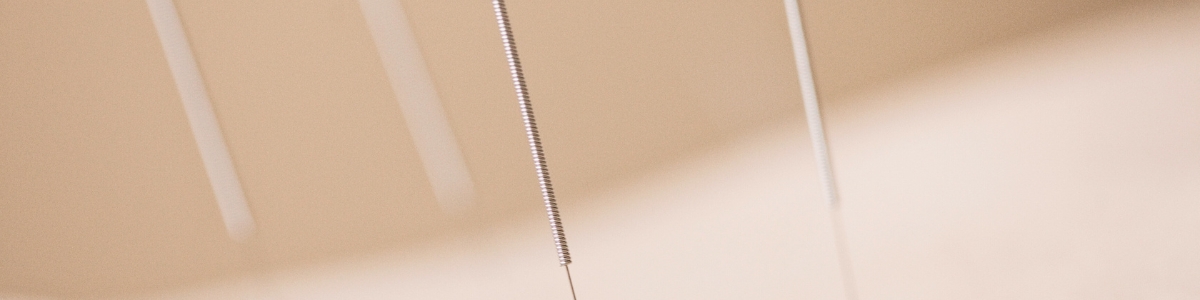

Het is bij acupunctuur van belang de (onderbewuste) oorzaak achter de klacht te vinden. Door op speciale plekken in het lichaam acupunctuur naalden te plaatsen vindt herstel plaats van de energiebalans.